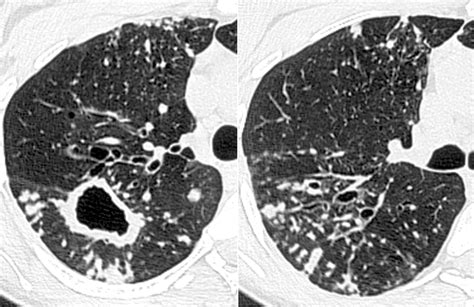

To differentiate between the various causes of tree in bud opacities, clinicians utilize a combination of clinical assessment and further diagnostic testing. The speed of onset is particularly helpful; an acute presentation (developing over days) often points toward an infection, whereas a chronic presentation (developing over months or years) might suggest bronchiectasis, cystic fibrosis, or chronic airway inflammation.

Once tree in bud opacities are identified, the management plan is tailored to the suspected underlying cause. For instance, if an infectious etiology is suspected, the physician may order sputum cultures, blood work, or, in some cases, a bronchoscopy to obtain a direct sample of the fluid or material causing the opacities.

If the finding is linked to a chronic condition like bronchiectasis, management may focus on airway clearance techniques, inhaled medications to open the airways, or long-term management of chronic inflammation. The goal of these interventions is to resolve the obstruction, clear the airways, and prevent further lung damage. It is rarely the case that this finding is ignored; the pattern serves as a sentinel that guides the physician toward the necessary diagnostic workup.